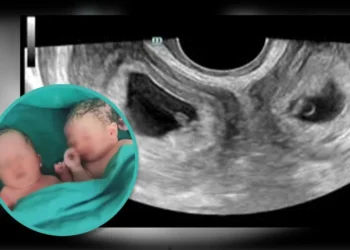

വടക്കു പടിഞ്ഞാറൻ മേഖല സ്വദേശിയായ യുവതിക്ക് രണ്ട് ​ഗർഭപാത്രം; അമ്പരന്ന് മെഡിക്കൽ വിദ​ഗ്ധർ

ഷാങ്സി: ഇരട്ടക്കുട്ടികൾക്ക് ജന്മം നൽകിയ ഒരു ചൈനീസ് യുവതി വാർത്താ തലക്കെട്ടുകളിൽ നിറയുകയാണ്. ഇരട്ടകൾക്ക് ജന്മം നൽകുന്നതിൽ അസ്വാഭാവികതയില്ലെങ്കിലും ഈ യുവതിയുടെ പ്രസവം മെഡിക്കൽ ലോകത്തെ തന്നെ...